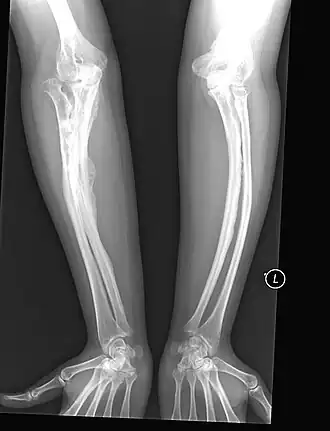

Остеосинтез штифтом

При остеосинтезе штифтом изогнутая кость сначала многократно остеотомируется, чтобы затем бусообразно нанизывать костные сегменты на интрамедуллярный гвоздь. Сначала для этого использовались жёсткие штифты. В растущей кости, однако, такие штифты приходилось периодически заменять, так как кость однажды становилась длиннее штифта, вследствие чего штифт не был больше способен служить поддержкой для кости. Следовали фрактуры в этих незащищённых областях. Поэтому в 1963 году ортопедами был сконструирован выдвижной штифт. При росте кости два сегмента штифта выдвигаются друг из друга по принципу устройства подзорной трубы и как бы растут вместе с костью.

- Показан остеосинтез штифтом, людям с частыми переломами одной и той же кости, с ложными суставами, а также имеющим средние и тяжёлые смещение или функциональное нарушение суставов.

- Противопоказан в том числе при тяжёлом общем состоянии, сердечно-дыхательной недостаточности или отсутствии возможности закрепления штифта в кости из-за недостатка костной ткани.